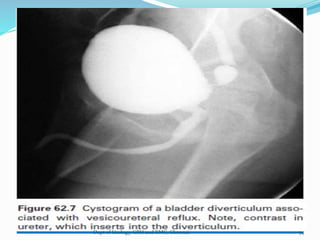

CONGENITAL BLADDER DIVERTICULA:

-diverticula measures >2cm in diameter in

IVU or voiding cystourethrogram

-saccules measures <2cm in diameter

-herniation of bladder mucosa through

the detrusor muscle

-98% congenital diverticula occurs in male

-most common in bladder base

-most frequently in the region of ureteral

hiatus known as Hutch diverticulum

-gives rise to obstruction or reflux

52

Associated anomalies :

-Ipsilateral Renal agenesis

-Ipsilateral undescended testis

Voiding cystourethrogram:

-diverticula are best shown

USG,CT,MRI: visible